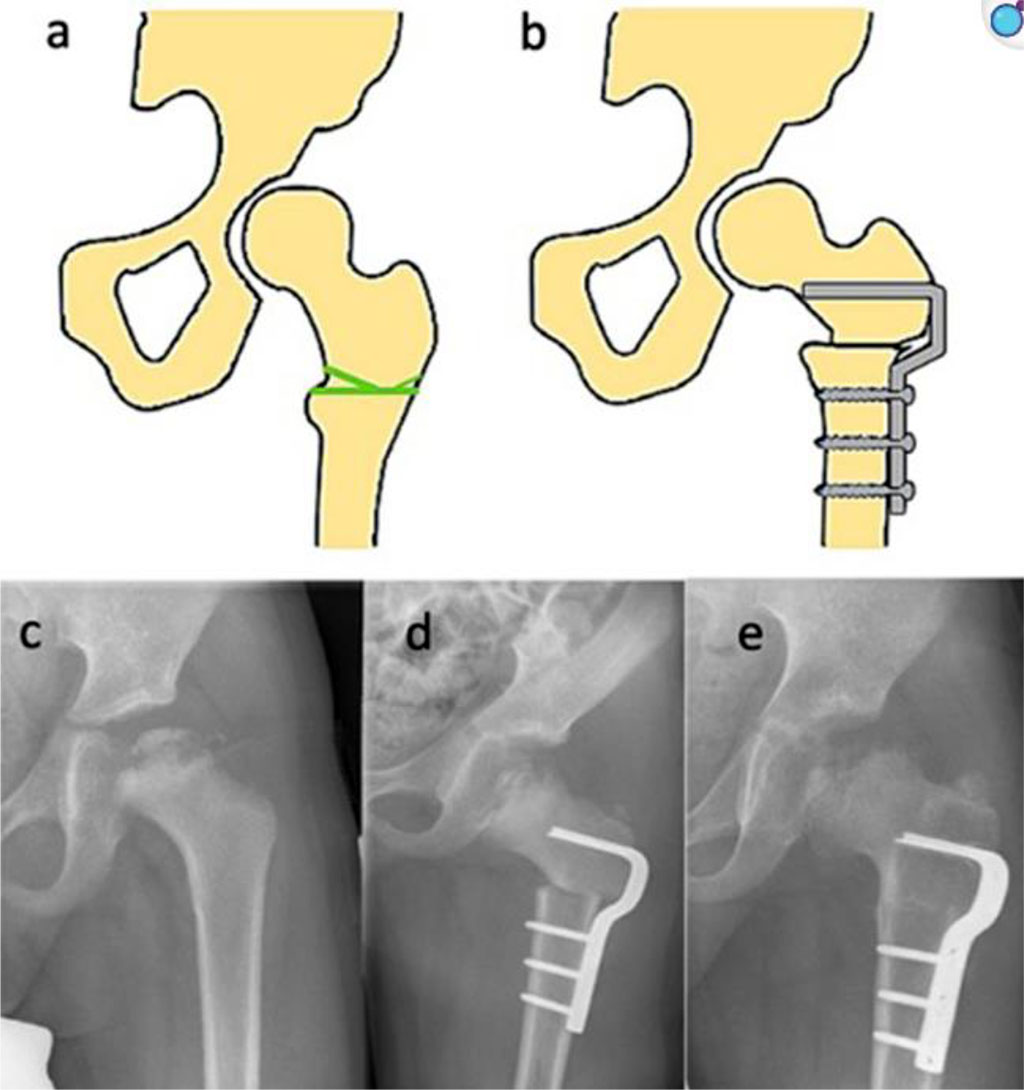

![Fig. 3 Femoral varus osteotomy (FVO) [40].](artikel-29-bild-3.jpg)

Fig. 3 Femoral varus osteotomy (FVO) [40].

One of the most commonly used surgical techniques in the treatment of LCPD is Femoral Varus Osteotomy (FVO). The goal of this procedure is to centralize the femoral head within the acetabulum, which promotes proper remodeling of its structure and can alter the natural course of the disease—particularly during the fragmentation stage—by slowing its progression to more advanced stages [41]. This technique was first described by Axer in 1963 and has since undergone numerous modifications. Today, the osteotomy is most commonly performed through an intertrochanteric approach, and advancements in stabilization techniques have allowed the replacement of traditional plates with more advanced implants featuring a predefined varus angle. The surgical method can be tailored based on the extent of necrosis affecting the femoral head. The operation offers several options for optimally positioning the femoral head within the acetabulum. Technical variations include correction in the frontal plane (varus angulation), sagittal plane (flexion-extension osteotomy), and transverse plane (derotational osteotomy), enabling precise alignment of the femoral head in the socket. These practices allow for an individualized approach based on patient anatomy. It is worth noting that this procedure is technically simpler to perform than pelvic osteotomies, which may influence the surgeon’s choice. However, FVO also has significant drawbacks. The most common complication is limb shortening on the operated side. Literature reports a typical discrepancy of approximately 1 cm, which may lead to gait disturbances. Furthermore, the surgery causes proximal displacement of the gluteus medius and minimus muscle attachments, potentially reducing muscle strength and contributing to the development of Trendelenburg gait and Duchenne’s intermittent claudication. For this reason, comprehensive postoperative physiotherapy is a crucial component of treatment. This includes the use of shoe lifts to equalize limb length, strengthening exercises for the gluteal muscle group, and maintenance of proper hip joint mobility [42, 43].

One of the most commonly used surgical techniques in LCPD is femoral varus osteotomy (FVO), aimed at centralizing the femoral head within the acetabulum and slowing disease progression. This procedure is technically simpler than pelvic osteotomies and can be modified according to individual anatomical conditions. However, it carries risks such as limb shortening and muscle weakness, making postoperative physiotherapy an essential part of recovery. Another method is the Salter innominate osteotomy (SIO), which improves femoral head coverage by redirecting part of the pelvis and stabilizing it—typically using Kirschner wires. However, these wires may migrate and lead to complications. An alternative is the use of absorbable screws, which do not require removal and reduce infection risk, though they are less stable than traditional wires. The triple pelvic osteotomy technique involves cutting all three pelvic bones to reorient the acetabulum without affecting joint biomechanics or limb length. However, it requires high surgical skill and carries a risk of significant blood loss. In severe or advanced cases, combined procedures on both the femur and pelvis are recommended. These offer the best chance of restoring normal hip joint function but also increase the risk of complications and prolong surgical time, which raises the likelihood of infection. There are numerous surgical techniques used to treat LCPD, varying in invasiveness, extent of intervention, and expected clinical outcomes. Each method has its strengths and limitations that must be considered during treatment planning. The choice of procedure should be individualized, taking into account the patient’s age, disease stage, clinical condition, and therapeutic goals. Equally important are the surgeon’s skills and experience, which can greatly influence the effectiveness of the chosen intervention. The available literature presents inconsistent findings regarding the effectiveness of different therapeutic strategies. Some studies indicate a superiority of surgical treatment, particularly in older patients and those in more advanced stages of the disease. Conversely, other reports suggest that conservative management in children under the age of six may yield comparable outcomes. The absence of randomized controlled trials (RCTs), however, means that most available conclusions are based on retrospective analyses and cohort studies, which substantially limits their evidentiary strength and hinders the formulation of definitive clinical recommendations [1, 40].